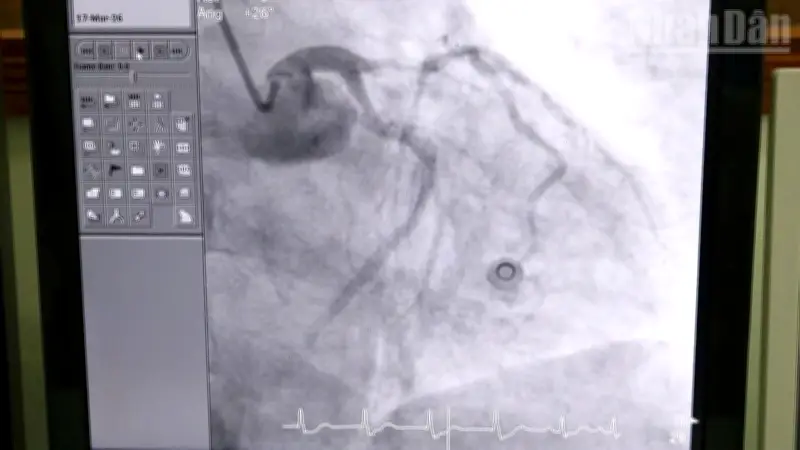

Kết quả chẩn đoán xác định bệnh nhân bị nhồi máu cơ tim cấp ST chênh lên vùng trước rộng, một trong những thể bệnh nặng nhất với nguy cơ tử vong rất cao. Các bác sĩ đã tiến hành chụp mạch vành, xử lý tổn thương và đặt stent nhằm tái thông dòng máu nuôi tim, giúp bệnh nhân dần hồi phục và trở lại trạng thái tỉnh táo.